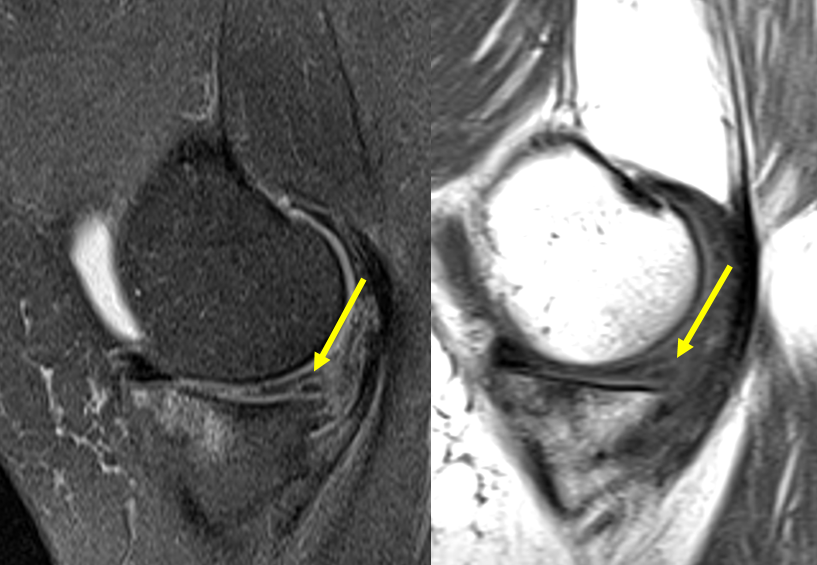

Coronal T2weighted MR image shows complete maceration of the body of Maceration Of Lateral Meniscus There are two menisci, which are. A lateral meniscus tear (torn meniscus) is a tear of the semicircular fibrous cartilage discs in the knee. Such lateral meniscus posterior horn lesions have been termed zip lesions. In one study, 97% of medial and 96% of lateral meniscal tears could be identified on sagittal mr images [1]. Lateral meniscus tears at the. Maceration Of Lateral Meniscus.

MENISCUS FIBRILLATION MRI LATERAL MENISCUS Radedasia Maceration Of Lateral Meniscus These lie on the inside (medial) and outside (lateral) edges of the top of your tibia (shin bone). When evaluating a knee mr examination, i study the medial and lateral menisci first on the sagittal images and then on the coronal images because sagittal images are the most useful in diagnosing meniscal tears. The lateral meniscus is a unique structure. Maceration Of Lateral Meniscus.

MENISCUS TEAR MACERATION DEGENERATION MRI KNEE RADIOLOGY (VIDEO Maceration Of Lateral Meniscus These lie on the inside (medial) and outside (lateral) edges of the top of your tibia (shin bone). A lateral meniscus tear (torn meniscus) is a tear of the semicircular fibrous cartilage discs in the knee. There are two menisci, which are. We describe a special, interesting phenomenon found in the anterior horn of the lateral meniscus (ahlm): In one. Maceration Of Lateral Meniscus.